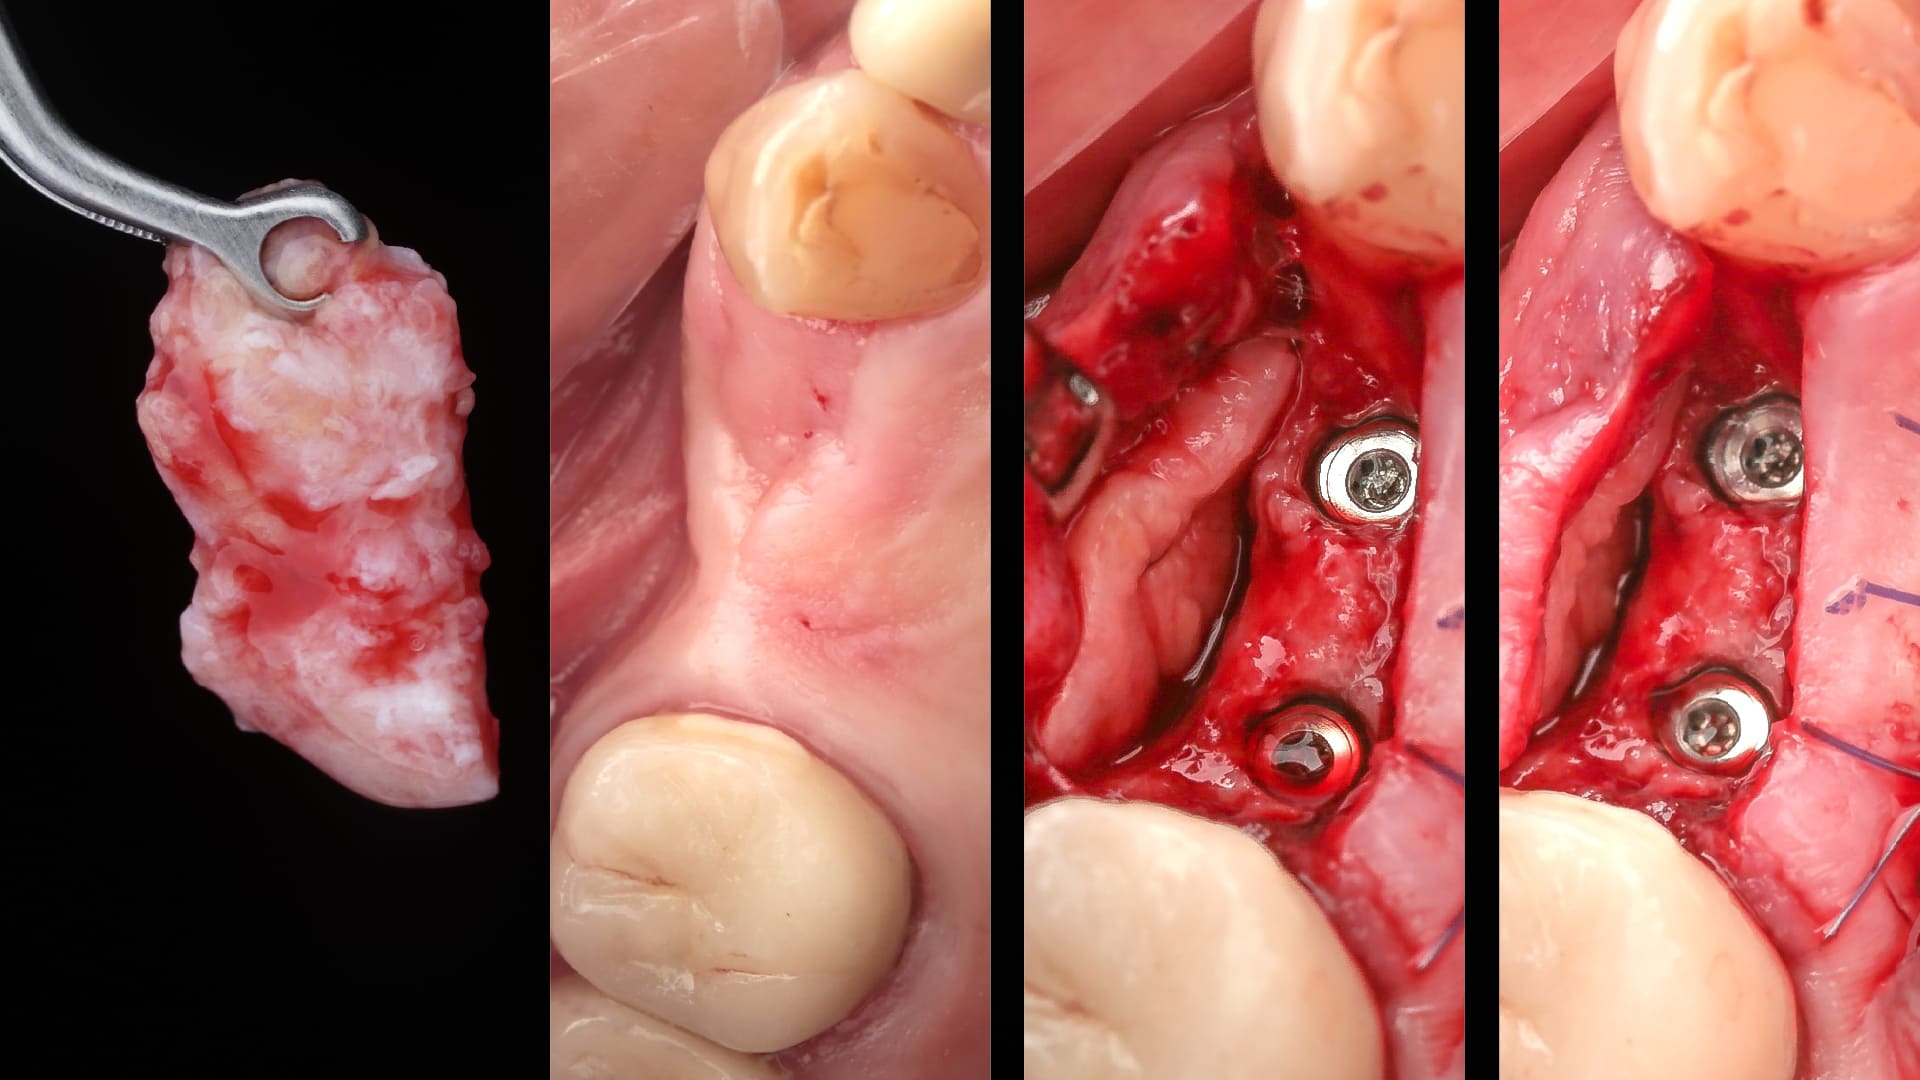

Immediate implant placement

Socket reconstruction with biomaterials and CTG

Management of the immediate provisional restorations contour

Customized healing in the posterior sites

Bone Reconstruction Simultaneously to Implant Placement​